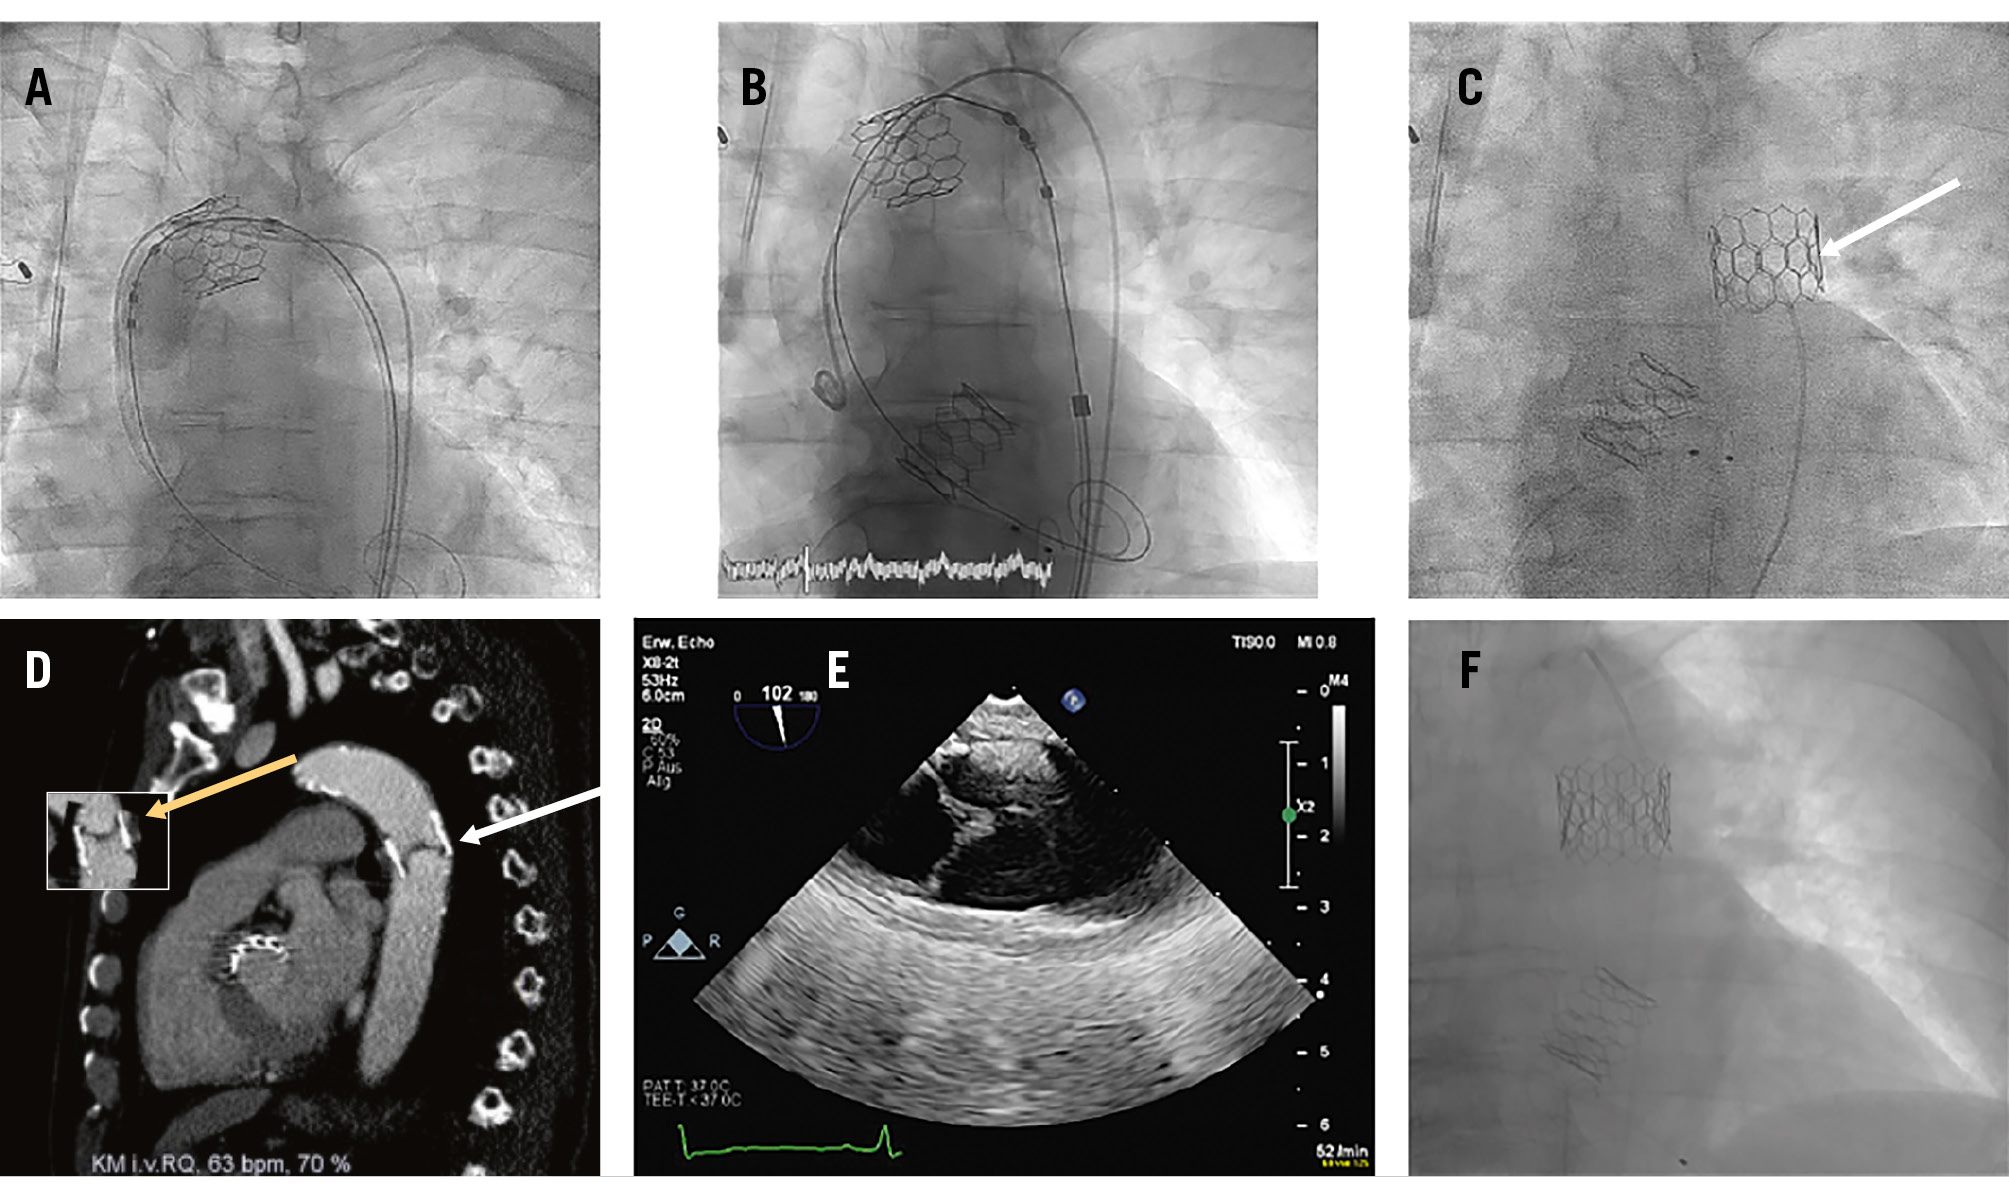

The TAVI procedure was performed in the early afternoon, between 12:40 pm and 1:25 pm. The patient was on permanent treatment with aspirin 100 mg/od and received unfractionated heparin during the procedure, which was controlled by activated clotting time measurement. During the implantation, the valve dislodged into the ascending aorta. Retrieval with a balloon into the descending aorta was not successful (Figure 1A) and a second 24.5 mm balloon-expandable Myval Octacor prosthesis was successfully implanted (Figure 1B). After withdrawal of the guidewire, spontaneous migration of the first valve into the descending aorta was seen. Due to the stable position of the dislodged valve (Figure 1C), the procedure was terminated, and the patient was transferred to an intermediate care unit, without any suspicious clinical signs. Palpable femoral pulses were documented during the late afternoon, and the patient received standard thromboembolic protection by subcutaneous low-molecular-weight heparin.

The next morning, at about 9 am, the patient complained of progressive paraplegia. Neurologists were contacted, who examined the patient, and a computed tomography (CT) scan was performed at 10 am. No abnormal finding was reported by the radiologists, nor by the neurologists, and a spinal cord embolisation was suspected (Figure 1D).

Due to persisting paraplegia, the CT scan was re-examined by our team at 2 pm, and an inversion of the dislodged prothesis was suspected (Figure 1D), leading to reduced peripheral and spinal perfusion. This was confirmed by the now-missing femoral pulses and by a transoesophageal echocardiography (Figure 1E).

We decided to implant a further 26 mm balloon-expandable Myval Octacor prosthesis, as a valve-in-valve procedure, into the dislodged prothesis, in the proper orientation (Figure 1F). Directly after the procedure, at 4:30 pm, femoral pulses could be palpated, and the paraplegia resolved within a week.

Re-examination of the initial implantation procedure revealed that the perforated longitudinal stent frames, indicating the upper row of the prosthesis, were proximally located (Figure 1C), indicating a twisted position of the valve within the descending aorta. The documented palpable pulses a few hours after the initial intervention as well as the initially missing pain and clinical symptoms may have been due to a persistent flow around the twisted dislodged valve. A small persisting flow besides the valve could still be documented in the transoesophageal echocardiography the following day, when symptoms were present (colour-coded Doppler image of the persistent flow not shown). We hypothesised that the twisted valve only slowly turned into an almost occlusive position, due to persistent pressure on the closed valve leaflets.

Figure 1. Sequelae of a dislodged balloon-expandable Myval Octacor aortic valve prosthesis. A) Unsuccessful retrieval attempt of the dislodged valve with a balloon into the descending aorta. B) Implantation of a second 24.5 mm balloon-expandable Myval Octacor prosthesis. C) Position of the spontaneously migrated valve in the descending aorta (white arrow: perforated longitudinal stent frames, indicating the upper row of the prosthesis, which suggest that the valve is in a twisted position). D) CT scan of the chest after beginning of symptoms, with inversion of the dislodged prothesis (white arrow: valve leaflets located at the lower distal end of the valve). The small picture shows how a “normal view” of a non-twisted prosthesis would look (yellow arrow: valve leaflets located at the upper proximal end of the valve). E) Confirmation of the twisted position of the dislodged valve by a transoesophageal echocardiography, showing the valve leaflets located at the lower distal end of the valve (on the left side; the right side is the cranial side of the picture). F) A further 26 mm Myval Octacor prosthesis implanted as a valve-in-valve, into the dislodged prothesis, in a proper orientation. CT: computed tomography